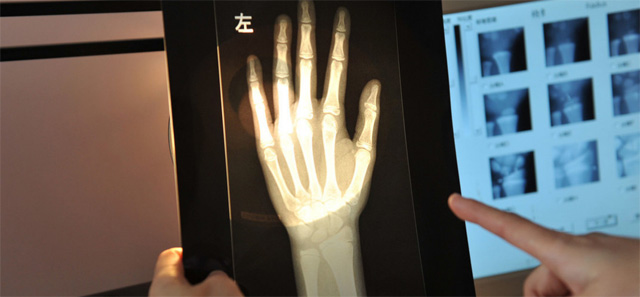

这个辐射到底对儿童有没影响呢?其实影响不大的,预测孩子的骨龄是对身高的评估。怎样监测,儿童在正常生长发育的过程中,随着年龄的增加。骨骼线会逐渐的钙化直至完全骨化,骨骼线闭合。骨龄是各个年龄骨的成熟度,正常情况下骨骼的年龄,和实际的年龄不应相差正负超过一岁。提前或者落后太多都是不正常的。用儿童的左手腕拍一张DR片来测骨龄,通过影像来观测儿童骨骼生长发育情况。预测儿童的生长发育潜力。这个骨龄监测是比较准确的。

还有精准骨骼线检查的位置在膝关节,通过DR拍片可以明确的看到骨骺线的状态。这就是为什么检查了手掌的骨骼线还有检查膝关节的。手掌的骨骼线闭合了,也不一定代表不能生长了,通过精准的骨骼线检查,判断儿童是否有长高的可能。膝关节骨骼线未闭合就可以进行身高的干预治疗。